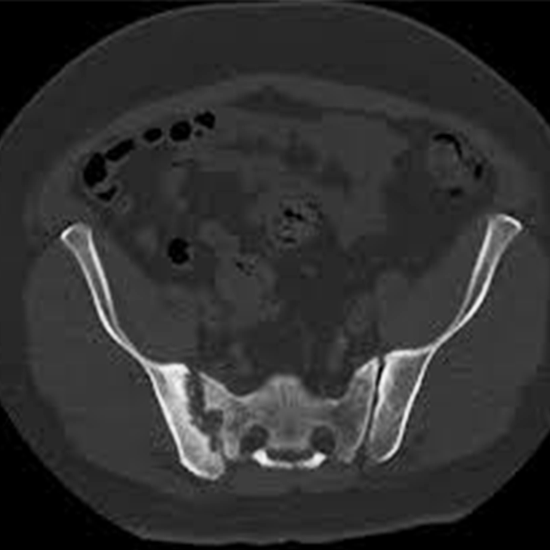

Sacroiliac Joints connect the pelvis and lower spine. It provides stability and attenuates force to the legs. To detect and diagnose the problems in both sacroiliac joints, a CT (Computed Tomography) Scan for the Bilateral Sacroiliac Joint is used.

CT Scan of Bilateral Sacroiliac Joint is an imaging diagnostic tool that is used to look for the conditions of the pelvis, lower spine and surrounding areas. Patients should not avoid any symptoms related to sacral joint injuries, abnormalities or disorders. Patients should go for screening to avoid any delay in diagnosis and treatment of the sacral joint.